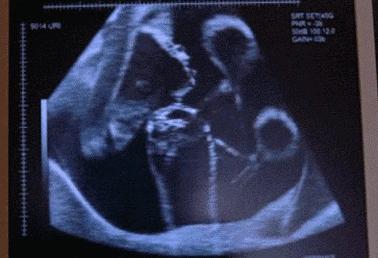

28岁的田女士与丈夫结婚已经6年了,记得在结婚那时,夫妻俩人就开始了造人计划并在不久就传来喜讯,可这样的欢乐没持续多久,在怀孕23周的时候,田女士肚子突然腹痛,而且阴道有出血的症状,家人赶紧把田女士送到医院,然而检查发现胎儿已经胎死腹中两周了。

但是在给田女士做清宫手术时,发现她体内的指标有些异常,不仅血压高、甲状腺功能、血钾低,并且在怀孕后就出现皮肤紫纹、痔疮的症状,经一系列的检查,最终找到孩子死亡的原因—脑垂体微腺瘤。

医生表示脑垂体肿瘤一般是育龄妇女患上比较多,如果在得知患有脑垂体肿瘤的女性,一定要及时手术治疗。并且除了脑垂体微腺瘤的疾病使胎儿胎死腹中,孕妇在孕期也要注意这些隐患,才能保证宝宝的顺利降生。